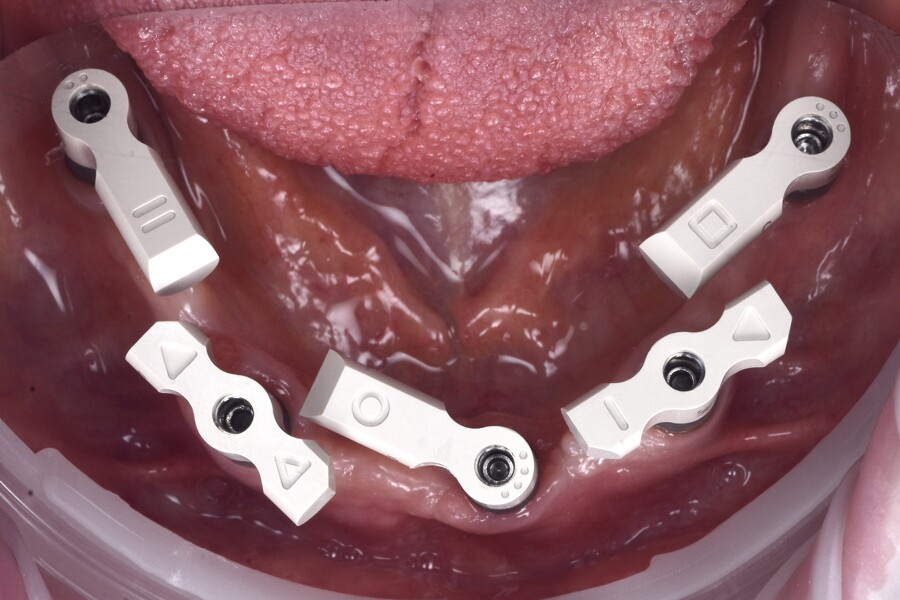

Sufficient primary stability was achieved, enabling immediate loading, consistent with evidence-based recommendations.2–6 SmartFlag scan bodies (Apollo Implant Components) were attached, and the postoperative intra-oral scan was performed with both the scan bodies and the osteosynthesis screws in place (Figs. 6 & 7). The screws were removed after scanning.

Fig. 6: Post-op scan with SmartFlags and osteosynthesis screws (circled).

The use of SmartFlag scan bodies intra-operatively further enhanced workflow accuracy. Compared with conventional vertical scan bodies, the SmartFlag’s compact, horizontal geometry and clearly defined reference surfaces enable superior scanner recognition and reduce scanner signal loss. The low-profile shape of SmartFlag minimises the need for frequent repositioning of the scanner and limits cumulative errors often associated with scanning long-span restorations. These properties were particularly advantageous in this full-arch mandibular case, enabling accurate digital capture of the implant positions. Postoperatively, a single intra-oral scan with the SmartFlag scan bodies was performed and digitally aligned with the preoperative scan using the fiducial markers. This facilitated the design and delivery of the immediately loaded provisional restoration with a passive, well-adapted fit. This protocol underscores the importance of preoperative planning and the integration of advanced tools like SmartFlag scan bodies to achieve predictable, reproducible outcomes in fully digital full-arch rehabilitation.